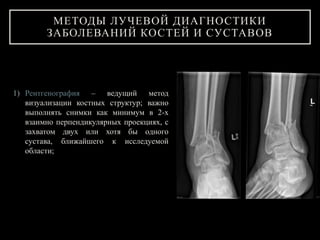

1) Рентгенография – ведущий метод

визуализации костных структур; важно

выполнять снимки как минимум в 2-х

взаимно перпендикулярных проекциях, с

захватом двух или хотя бы одного

сустава, ближайшего к исследуемой

области;

МЕТОДЫ ЛУЧЕВОЙ ДИАГНОСТИКИ

ЗАБОЛЕВАНИЙ КОСТЕЙ И СУСТАВОВ